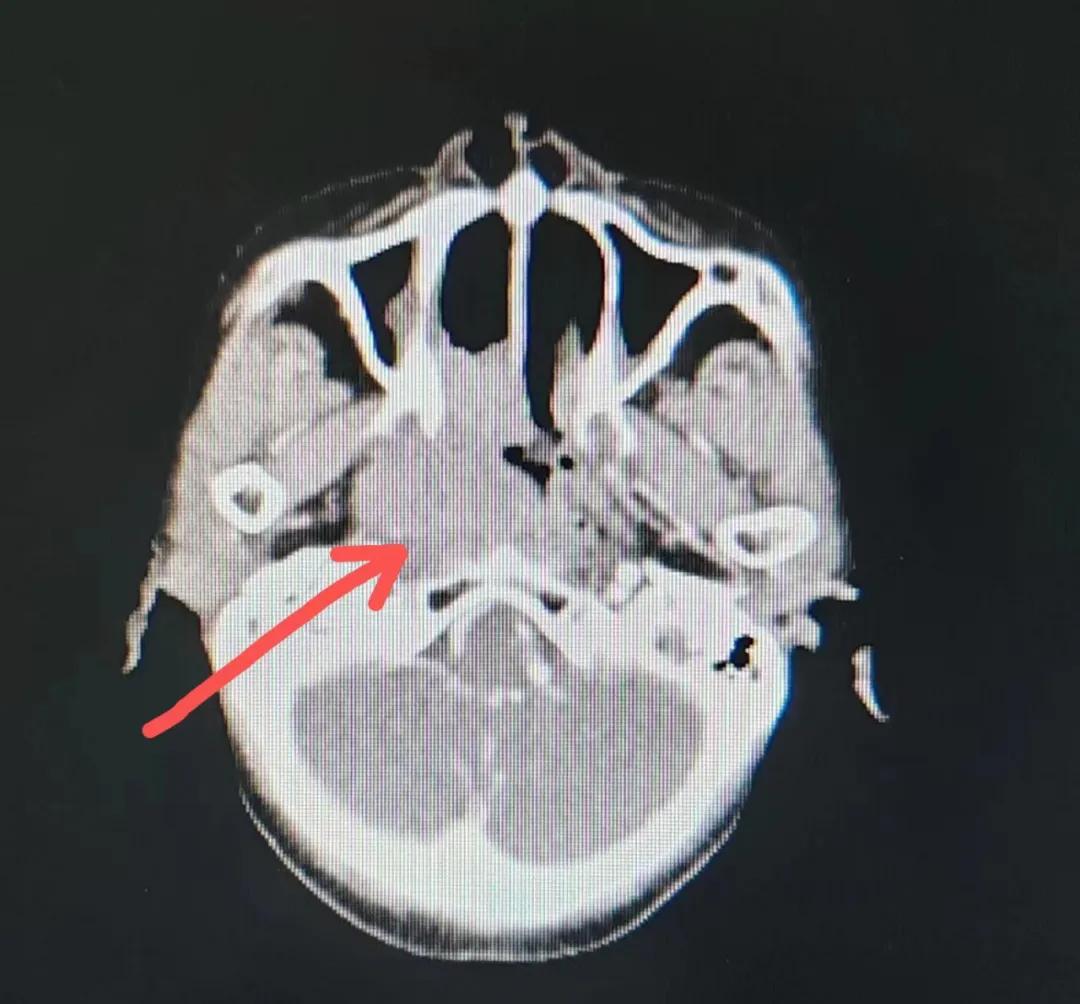

治療后

放療結束,除了放療處的皮膚輕微放射性皮炎外,基本沒有什么不良反應。復查發現,鼻腔淋巴瘤已不可見,目前患者已康復出院。